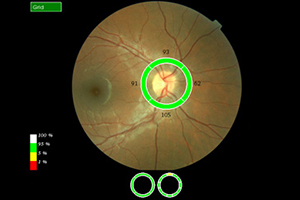

Nervenfaseranalyse (OCT)

Die Untersuchung am OCT ist ähnlich einem Foto ohne Blitz und dauert nur wenige Minuten. Sie erfolgt absolut schmerzfrei und ohne Berührung der Augen. Die Netzhaut wird um den Sehnerven durch ein Laserverfahren in optische Schnitte zerlegt und es kann damit wie bei einem mikroskopischen Gewebeschnitt die Netzhaut des Auges beurteilt werden. Das OCT führt eine objektive Messung der Nervenfaserschicht durch, da es keine Mitarbeit des Patienten verlangt. Das OCT zeigt frühzeitig ein Glaukom an, sogar wenn das Sehvermögen noch nicht beeinträchtigt ist.

Bei ca. 9-15 monatigen Folgeuntersuchungen kann dann ein Fortschreiten bzw. Stillstand bei entsprechender Therapie festgestellt werden.

Nervenfaseranalyse – Augenärztliche Gemeinschaftspraxis | Dr. Heuring, Dr. Jung & Kollegen

Ausdruck OCT: normale Papille mit normaler Nervenfaserschicht